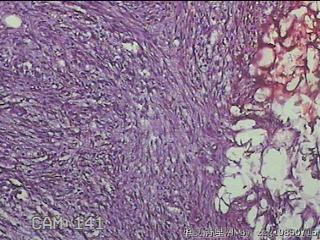

性别

男

年龄

39

临床诊断

左肘部肿物:炎性脂肪瘤

一般病史

发现左肘部肿物1周。

标本名称

左肘部包块

大体所见

灰白粉红色组织2x1.8x0.3㎝一团,表面结节状,光滑,切面灰白粉红色,质软。

纤维组织细胞瘤

有外伤史吗,考虑结节性筋膜炎。

首先考虑结节性筋膜炎。

梭形细胞肿瘤,待免疫组化